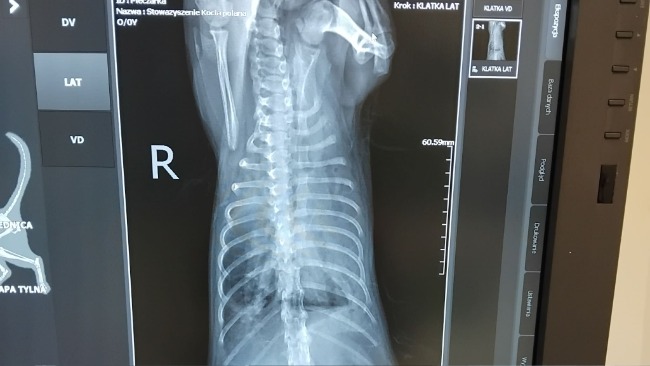

Jak już wiecie nasza mała koteczka Pieczarka czyli Kicisława ma cały czas problemy zdrowotne, nadal nie wiemy co jest ich przyczyną i staramy się robić wszystko aby miała szanse na normalne, długie i szczęśliwie życie.

To maleństwo ma teraz 18 tygodni, waży troche ponad 1,5kg ale wolę życia i miłość do człowieka ma ogromną.

Wykonalismy tomografię, posiewy, bdania krwi, usg kontrolne, a ostatnio miała punkcję osierdzia iściągnięcie płyku, którego jeszcze tydzień temu nie było, teraz czekamy na wyniki, może wreszcie dowiemy z czym ona i my walczymy.